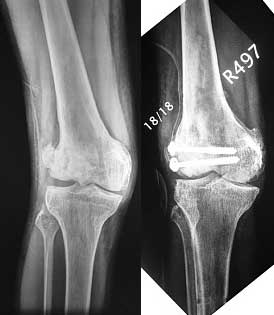

This was fixed temporarily, bone grafted with tricortical struts, and fixed by two cancellous screws. The fragment was not large enough to afford any fixation to a plate or such implant, and the screws held it compressed well to the rest of the distal femur.

Post-op - limb is well aligned, rom 0-30, but I am not pushing that right now, for the next two or three weeks.

Further plan - hope that the screws hold the fragment appropriately till union, but if the stability on table is anything to judge by, that should not be a problem.

Pictures attached.